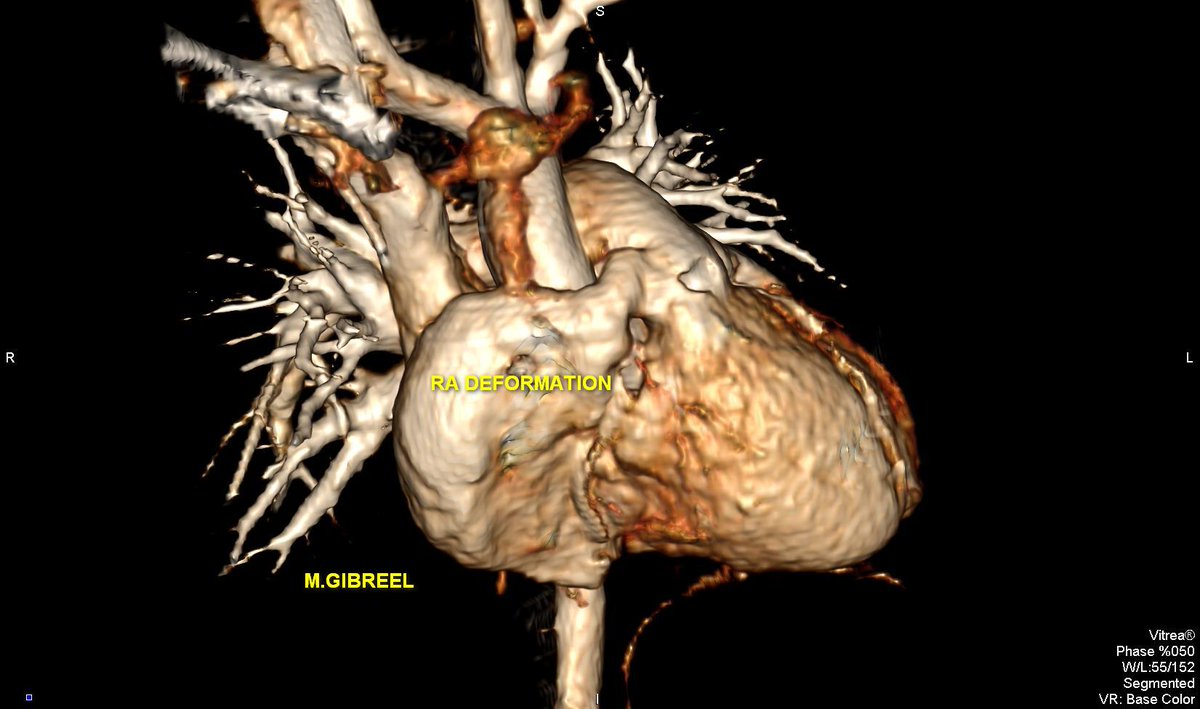

Subsequent chamber deformation : Two patients,,, RV & RA geometric deformation in pectus excavatum,,, From my archive

MGibreel1's tweet image. Subsequent chamber deformation :

Two patients,,,

RV & RA geometric deformation in pectus excavatum,,,

From my archive